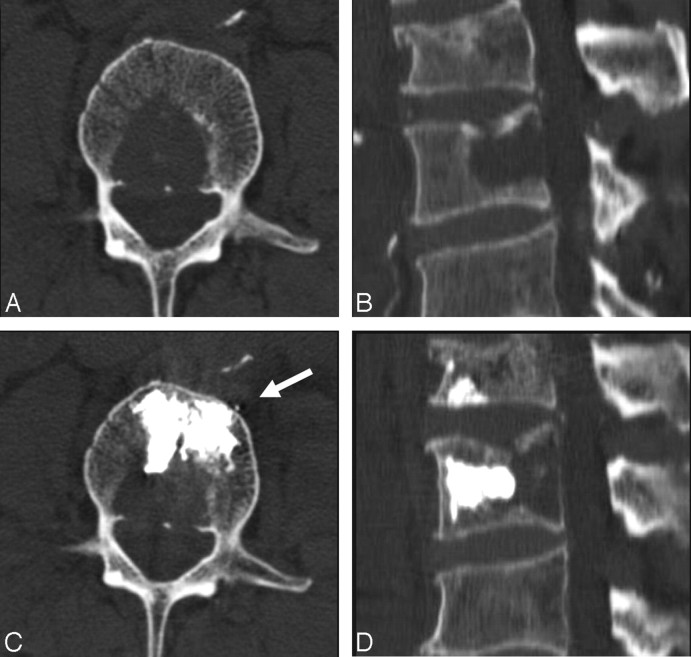

Fig 3.

A 83-year-old man with a history of lymphoma. A and B, Axial and sagittal reconstruction CT scans show the lytic lesion in the posterior part of the L2 vertebral body. C and D, The corresponding CT scans obtained immediately after the procedure show all the injected cement in the anterior two thirds of the vertebral body and anterior to the lytic lesion. Arrow shows minimal anterior venous leakage.